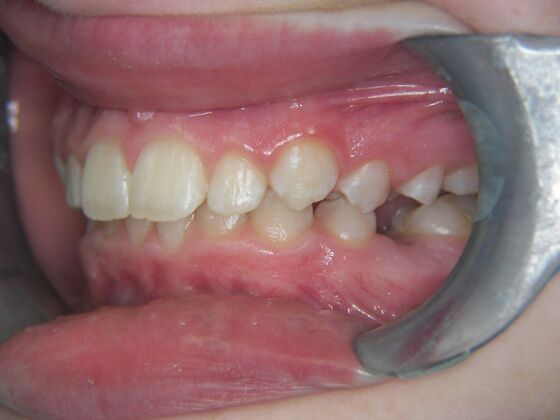

Orthodontics: Case 2

Patient is 9 years old and presents with 100% overbite and blocked out upper and lower lateral incisors. Both upper central incisors are palatally inclined causing a lack of space available for most anterior teeth. Advised her parents that she needs Phase I Interceptive Orthodontic treatment to provide room for all upper and lower front teeth. Phase I treatment was begun and finished, then began Phase II treatment shortly thereafter to finalize case. Removable retainer were fabricated for retention.